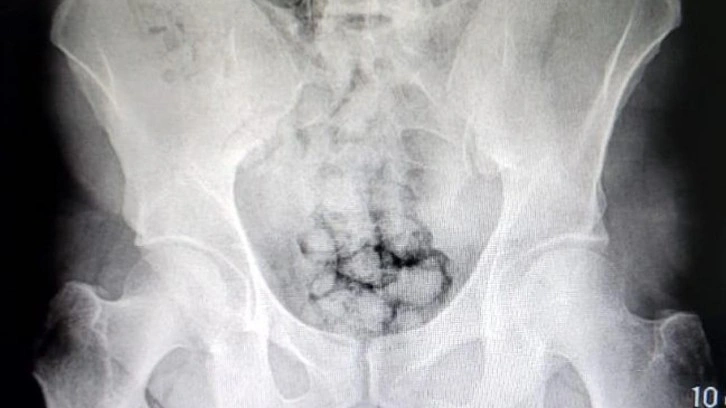

Muayene edilmek üzere Kayseri Devlet Hastanesi'ne getirilen 2 şüphelinin röntgenleri çekildi. Röntgen çekimi sonrası şüphelilerin midesinde yaklaşık 60 kapsül içinde toplam 500 gram metamfetamin olduğu tespit edildi. Uyuşturucular sağlık ekiplerince yapılan tedavinin ardından çıkarıldı. Gözaltına alınan şüpheliler, tedavi işlemlerinin ardından polis merkezine götürüldü.